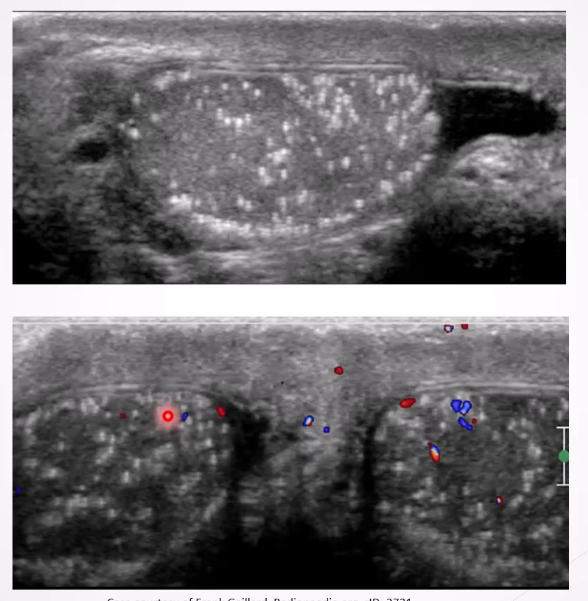

Varicocele: Dilatation of the pampiniform plexus of veins within the spermatic cord and the most common mass of the spermatic cord. Most common cause of male infertility

Causes: most are primary resulting from incompetent or congenitally absent valves in the testicular vein.

Secondary varicoleles less common and reuslt from increased pressure in testicular vein due to compression from renal enal mass, lymphadenopathy or renal vein compression in nutcracker syndrome

Left testicles more affected than the right due to the anatomical differences in venous drainage, leading to a higher incidence of varicocele on the left side.

Clinical Presentation: Can be asymptomatic; symptoms may include scrotal mass/swelling, pain, testicular atrophy, and infertility.

Ultrasound Appearance:

Dilated veins >2-3 mm in diameter

Scrotal mass with a "Bag of worms" appearance above or posterior to the testes

Veins increase in size with Valsalva maneuver.